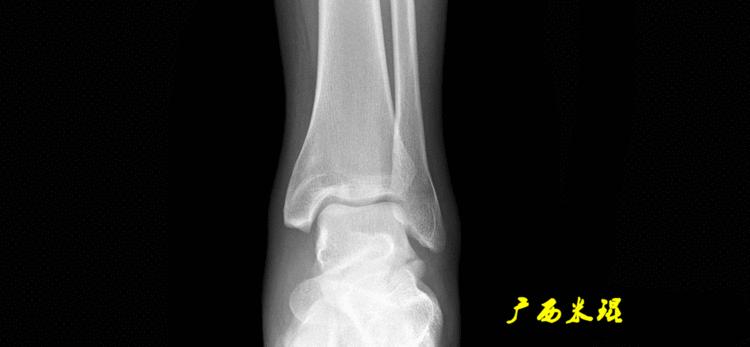

(3)踝关节中心

踝关节中心点常用的也有3个,分别是骨骼(内、外踝表面间距)中点、踝关节间隙水平软组织中点和距骨宽度中点。

(4)踝关节线

踝关节线为胫骨远端软骨下骨之间的连线。

胫骨远端外侧角(mLDTA):胫骨远端切线(关节线)与下肢力线(机械轴)两者之间的外侧夹角,正常为89°±3°。